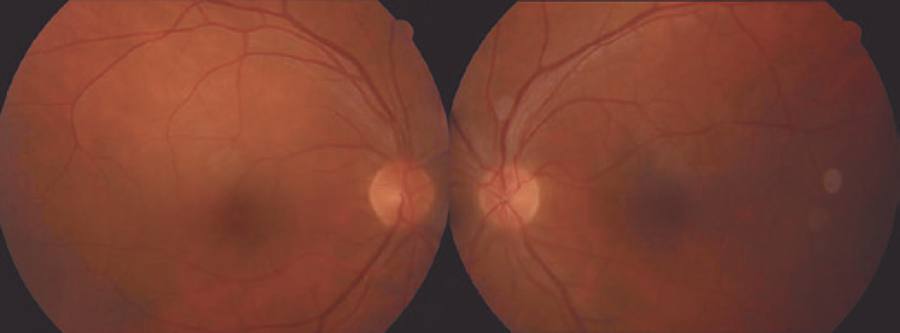

A 44-year-old male patient presented to our clinic with symptoms of floaters in both eyes for a week. The best corrected visual acuity (BCVA) was 0.8 on the right eye and 0.9 on the left, and intraocular pressures were normal. The case had been followed up for mucosal LP for the last 10 years at another center. Anterior segment examination was normal for both eyes. Bilateral intensive vitritis and peripheral vascular sheathing were observed on fundus examination (Figure 1). FA investigation revealed staining and leakage of the mid-peripheral vessels in the early stage and of the optic disc and surrounding vessels in the late stage (Figure 2). The patient had no history of urogenital or oral ulceration, skin rash, weight loss, cough, night sweats, lymphadenopathy, arthritis, arthralgia, neurological symptoms, gastrointestinal symptoms, travel to foreign territories, or contact with animals. No evidence of pathology was found in tests performed to investigate the etiology of retinal vasculitis, and complete blood count, biochemical tests (glucose, urea, creatinine, electrolytes, and liver and kidney function tests), erythrocyte sedimentation, C-reactive protein, FTA-ABS, VDRL, Lyme IgM and IgG, HIV serology, urine analysis, rheumatoid factor (RF), anti-neutrophil antibody (ANA), tuberculin skin test (PPD), and chest X-ray tests were all normal. The results of cranial and orbital magnetic resonance imaging were normal. Consultations with various departments were performed to exclude Behcet's disease, sarcoidosis, systemic lupus erythematosus, multiple sclerosis, and tuberculosis, some of the most common etiologic causes of retinal vasculitis. Because of suspected LP, fluocortolone tab (1 mg/kg), cyclosporine tab (2 x 100 mg), and azathioprine tab (2 x 50 mg) were started as systemic treatment. No topical treatment was used. Corticosteroid treatment was gradually decreased and eventually stopped. BCVA fully recovered bilaterally at the first month of follow-up, and the vitritis and peripheral vascular sheathing had regressed. BCVA and anterior and posterior segment examinations were normal within the first year follow-up; therefore, the immunosuppressive treatment was discontinued (Figure 3).